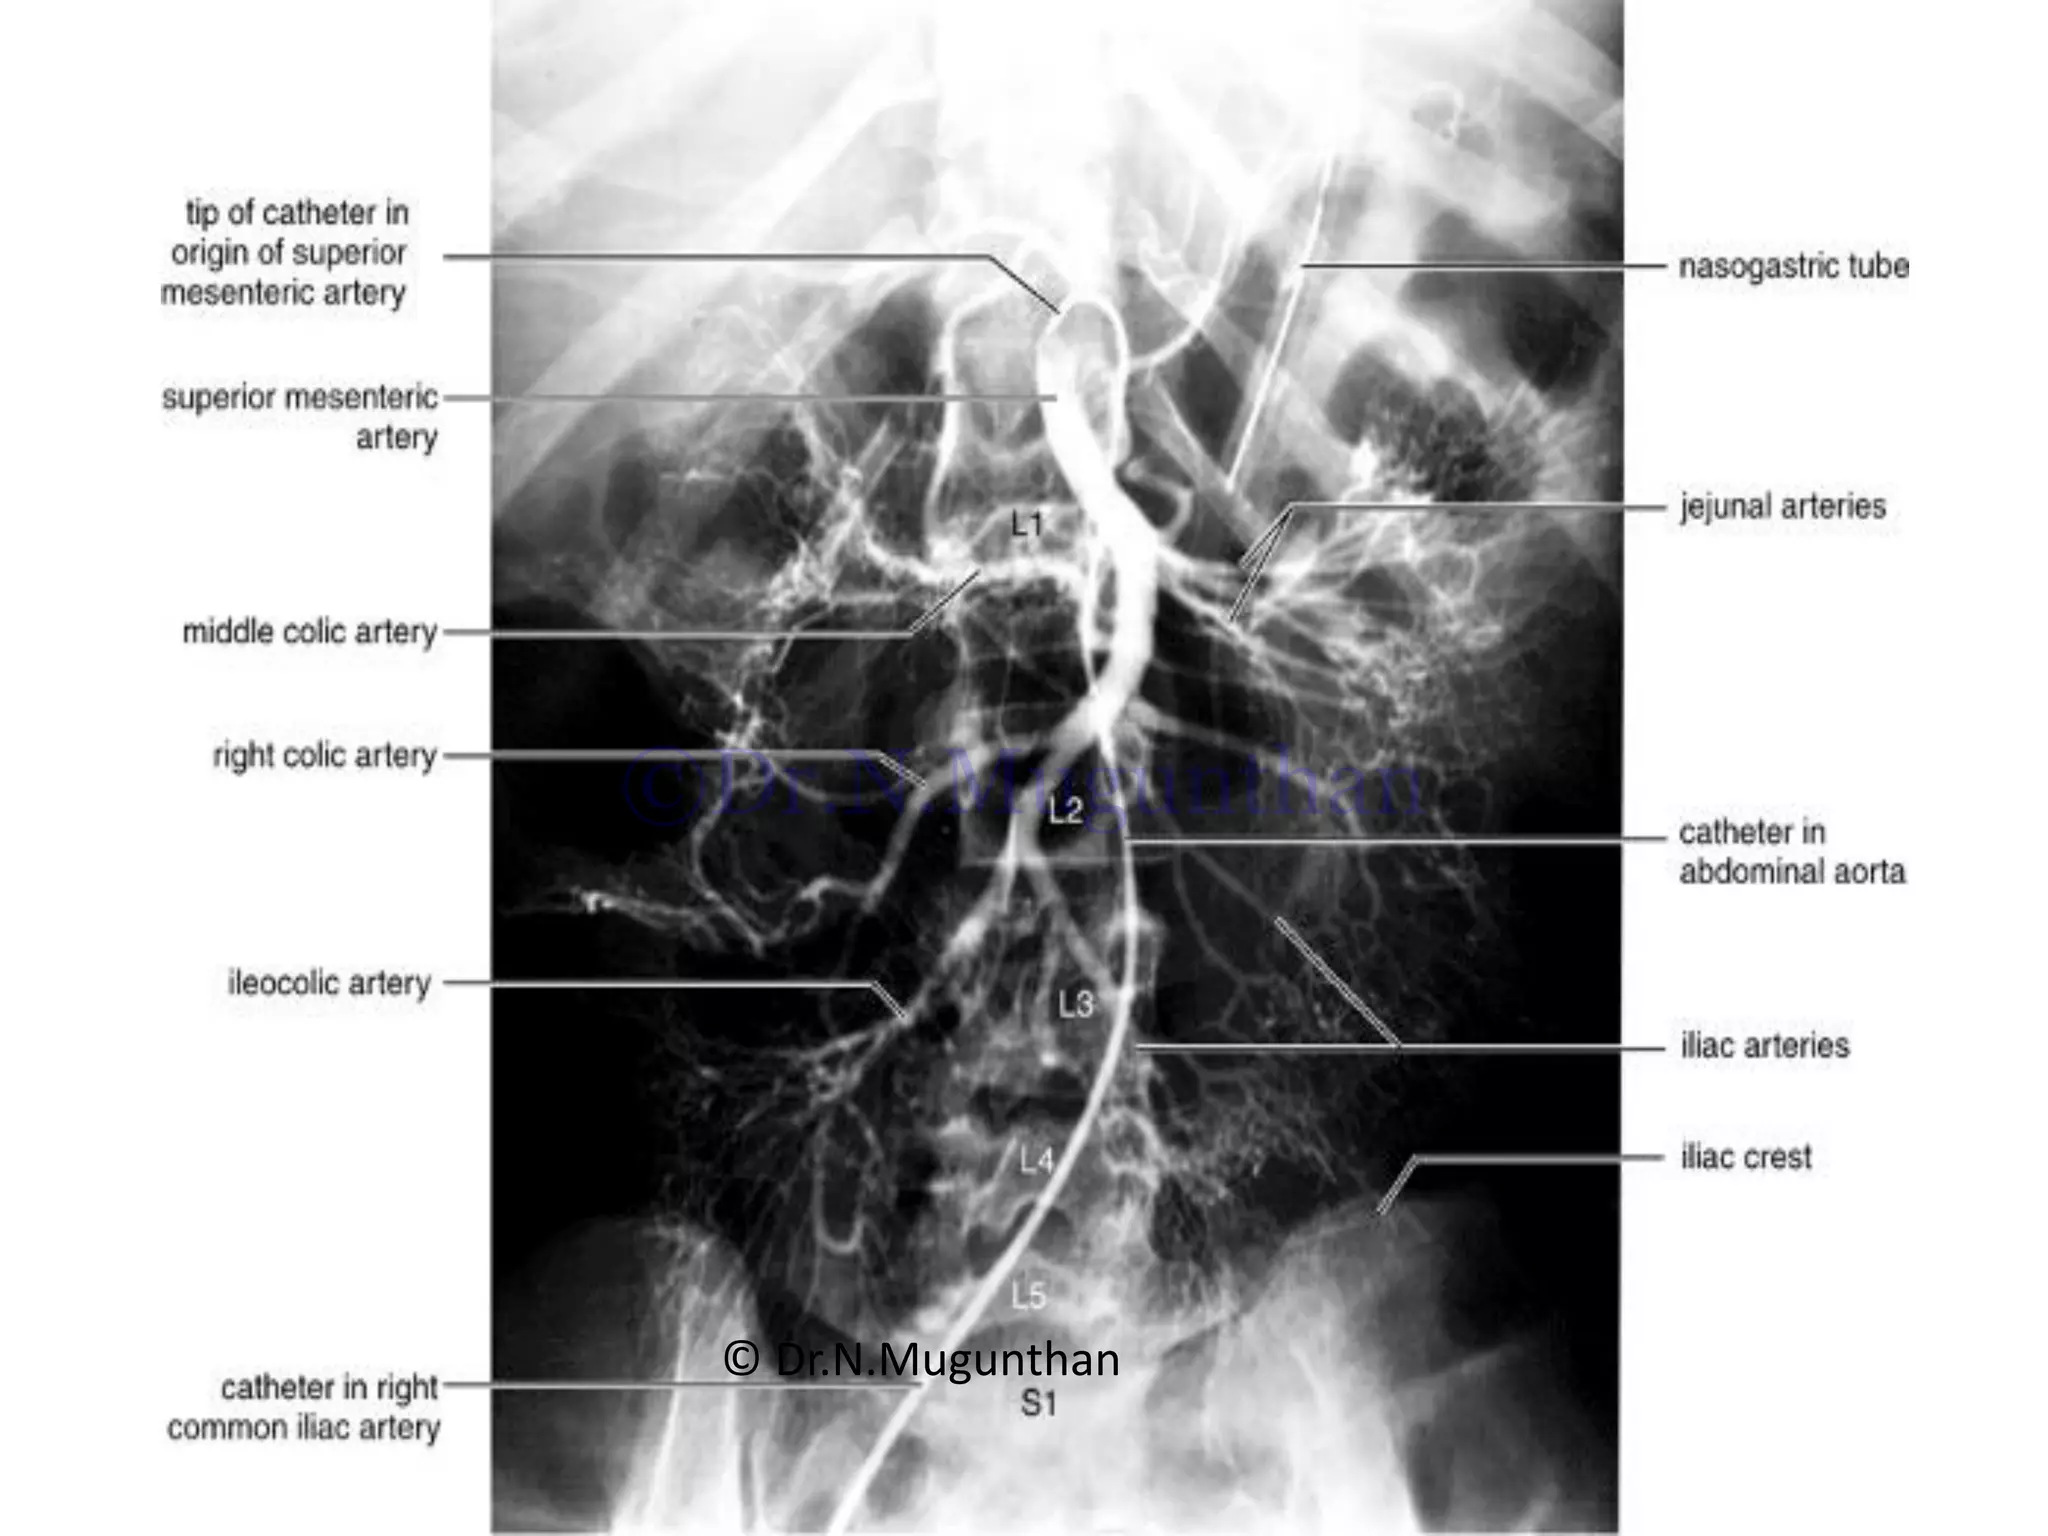

SUPERIOR MESENTERIC ARTERY

Origin:

Course & relations:

• Downwards, forwards and to the right

infront of

• Uncinate process of pancreas 3rd part

of duodenum,

• IVC

• Rt.Psoas

• Rt.Ureter

• Runs along the root of mesentery to

rt.Iliac fossa.

Termination:

• Ends by joining with its ileocolic

branch. © Dr.N.Mugunthan

Branches:

• Inferior pancreatico-

duodenal artery

• Jejunal branches (5-6)

• Ileal branches (6-8)

• Ileo-colic artery

o Ant.caecal, post.caecal &

appendicular artery

• Rt.colic artery.

• Middle colic artery.

Summary of SMA:

• SMA –artery of mid gut

• Supplies entire small gut

except the proximal part of

duodenum upto the ampulla

of vater

• Supplies large gut upto the

junction of rt.2/3rd and left

1/3rd of the transverse colon

• Also supplies lower part of

head of the pancreas.